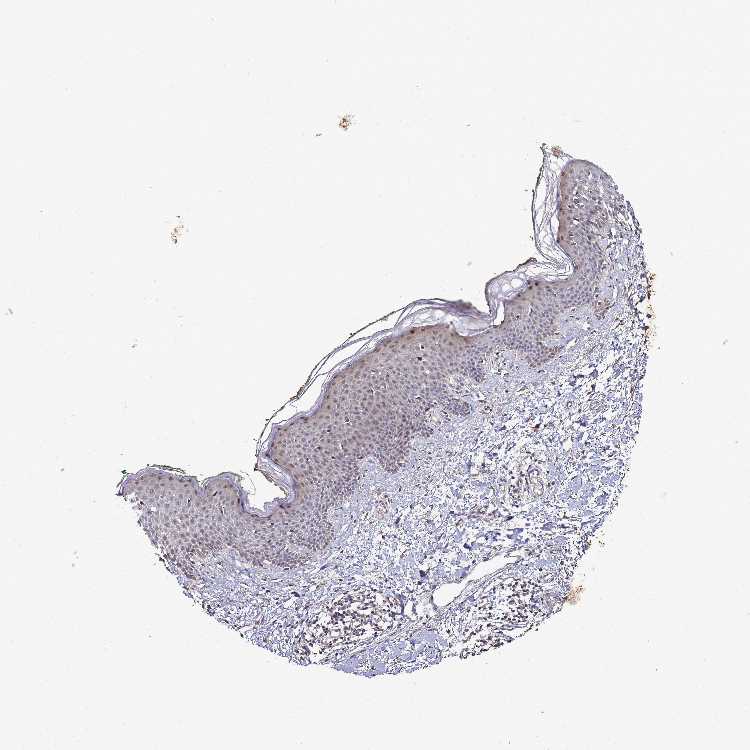

SKIN 1 - Antibody stainingi

Antibody staining in the annotated cell types in the current human tissue is reported as not detected, low, medium, or high, based on conventional immunohistochemistry profiling in selected tissues. This score is based on the combination of the staining intensity and fraction of stained cells.

Each image is clickable and will lead to virtual microscopy that enables deeper exploration of all samples and also displays staining intensity scores, fraction scores and subcellular localization as well as patient and tissue information for each sample.

Antibody HPA042116Antibody HPA043556

Langerhans MediumNot detected

Fibroblasts Not detectedNot detected

Keratinocytes MediumMedium

Melanocytes MediumMedium

SKIN 2 - Antibody stainingi

Epidermal cells LowMedium